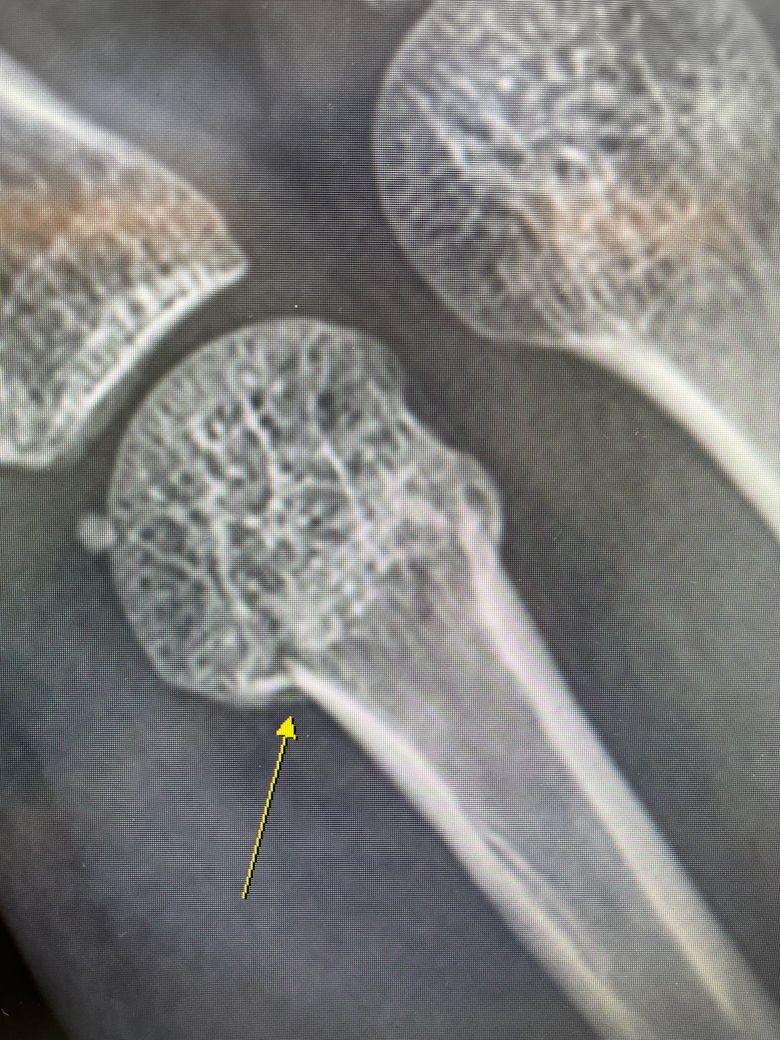

지난주 목요일 친구와 장난을 치다가 철문을 오른손 주먹으로 가격한 이후 부어올라 동네 병원을 방문했더니 복서골절이라는 진단을 받았습니다

교정치료를 진행하고 교정이 잘 되지않아 수술을 하여야 할 것 같다며 큰병원으로 가라고 이야기해주셨는데요 해당 골절의 경우 수술이 꼭 필요할까요? 통증도 별로 없고 많이 붓지도 않아 저는 최대한 깁스만으로 회복하고 싶습니다.

• 1번 째 사진

복서골절은 골절 각도, 뼈의 어긋남, 손가락 기능 제한 여부에 따라 수술 여부가 결정됩니다. 통증이 적어도 골절이 심하게 휘었거나 관절 정렬이 틀어지면 수술이 필요할 수 있습니다.

굴곡 각도가 30~40도 이상인 경우나 혹은 손의 회전 변형이 발생하거나 복합골절 또는 골편 간 간격이 크거나 비수술적인 치료를 하였지만 효과가 없거나 하면 수술적인 치료를 고려해볼 수 있습니다.

통증이 적다고 해서 괜찮은 것은 아니며 손의 작은 뼈는 신경이 덜 자극되는 위치라서 심한 골절이어도 통증이 약할 수 있으며 나중에 기능장애가 생기면 되돌리기 어려워 초기에 잘 맞춰 놓는 것이 매우 중요합니다.